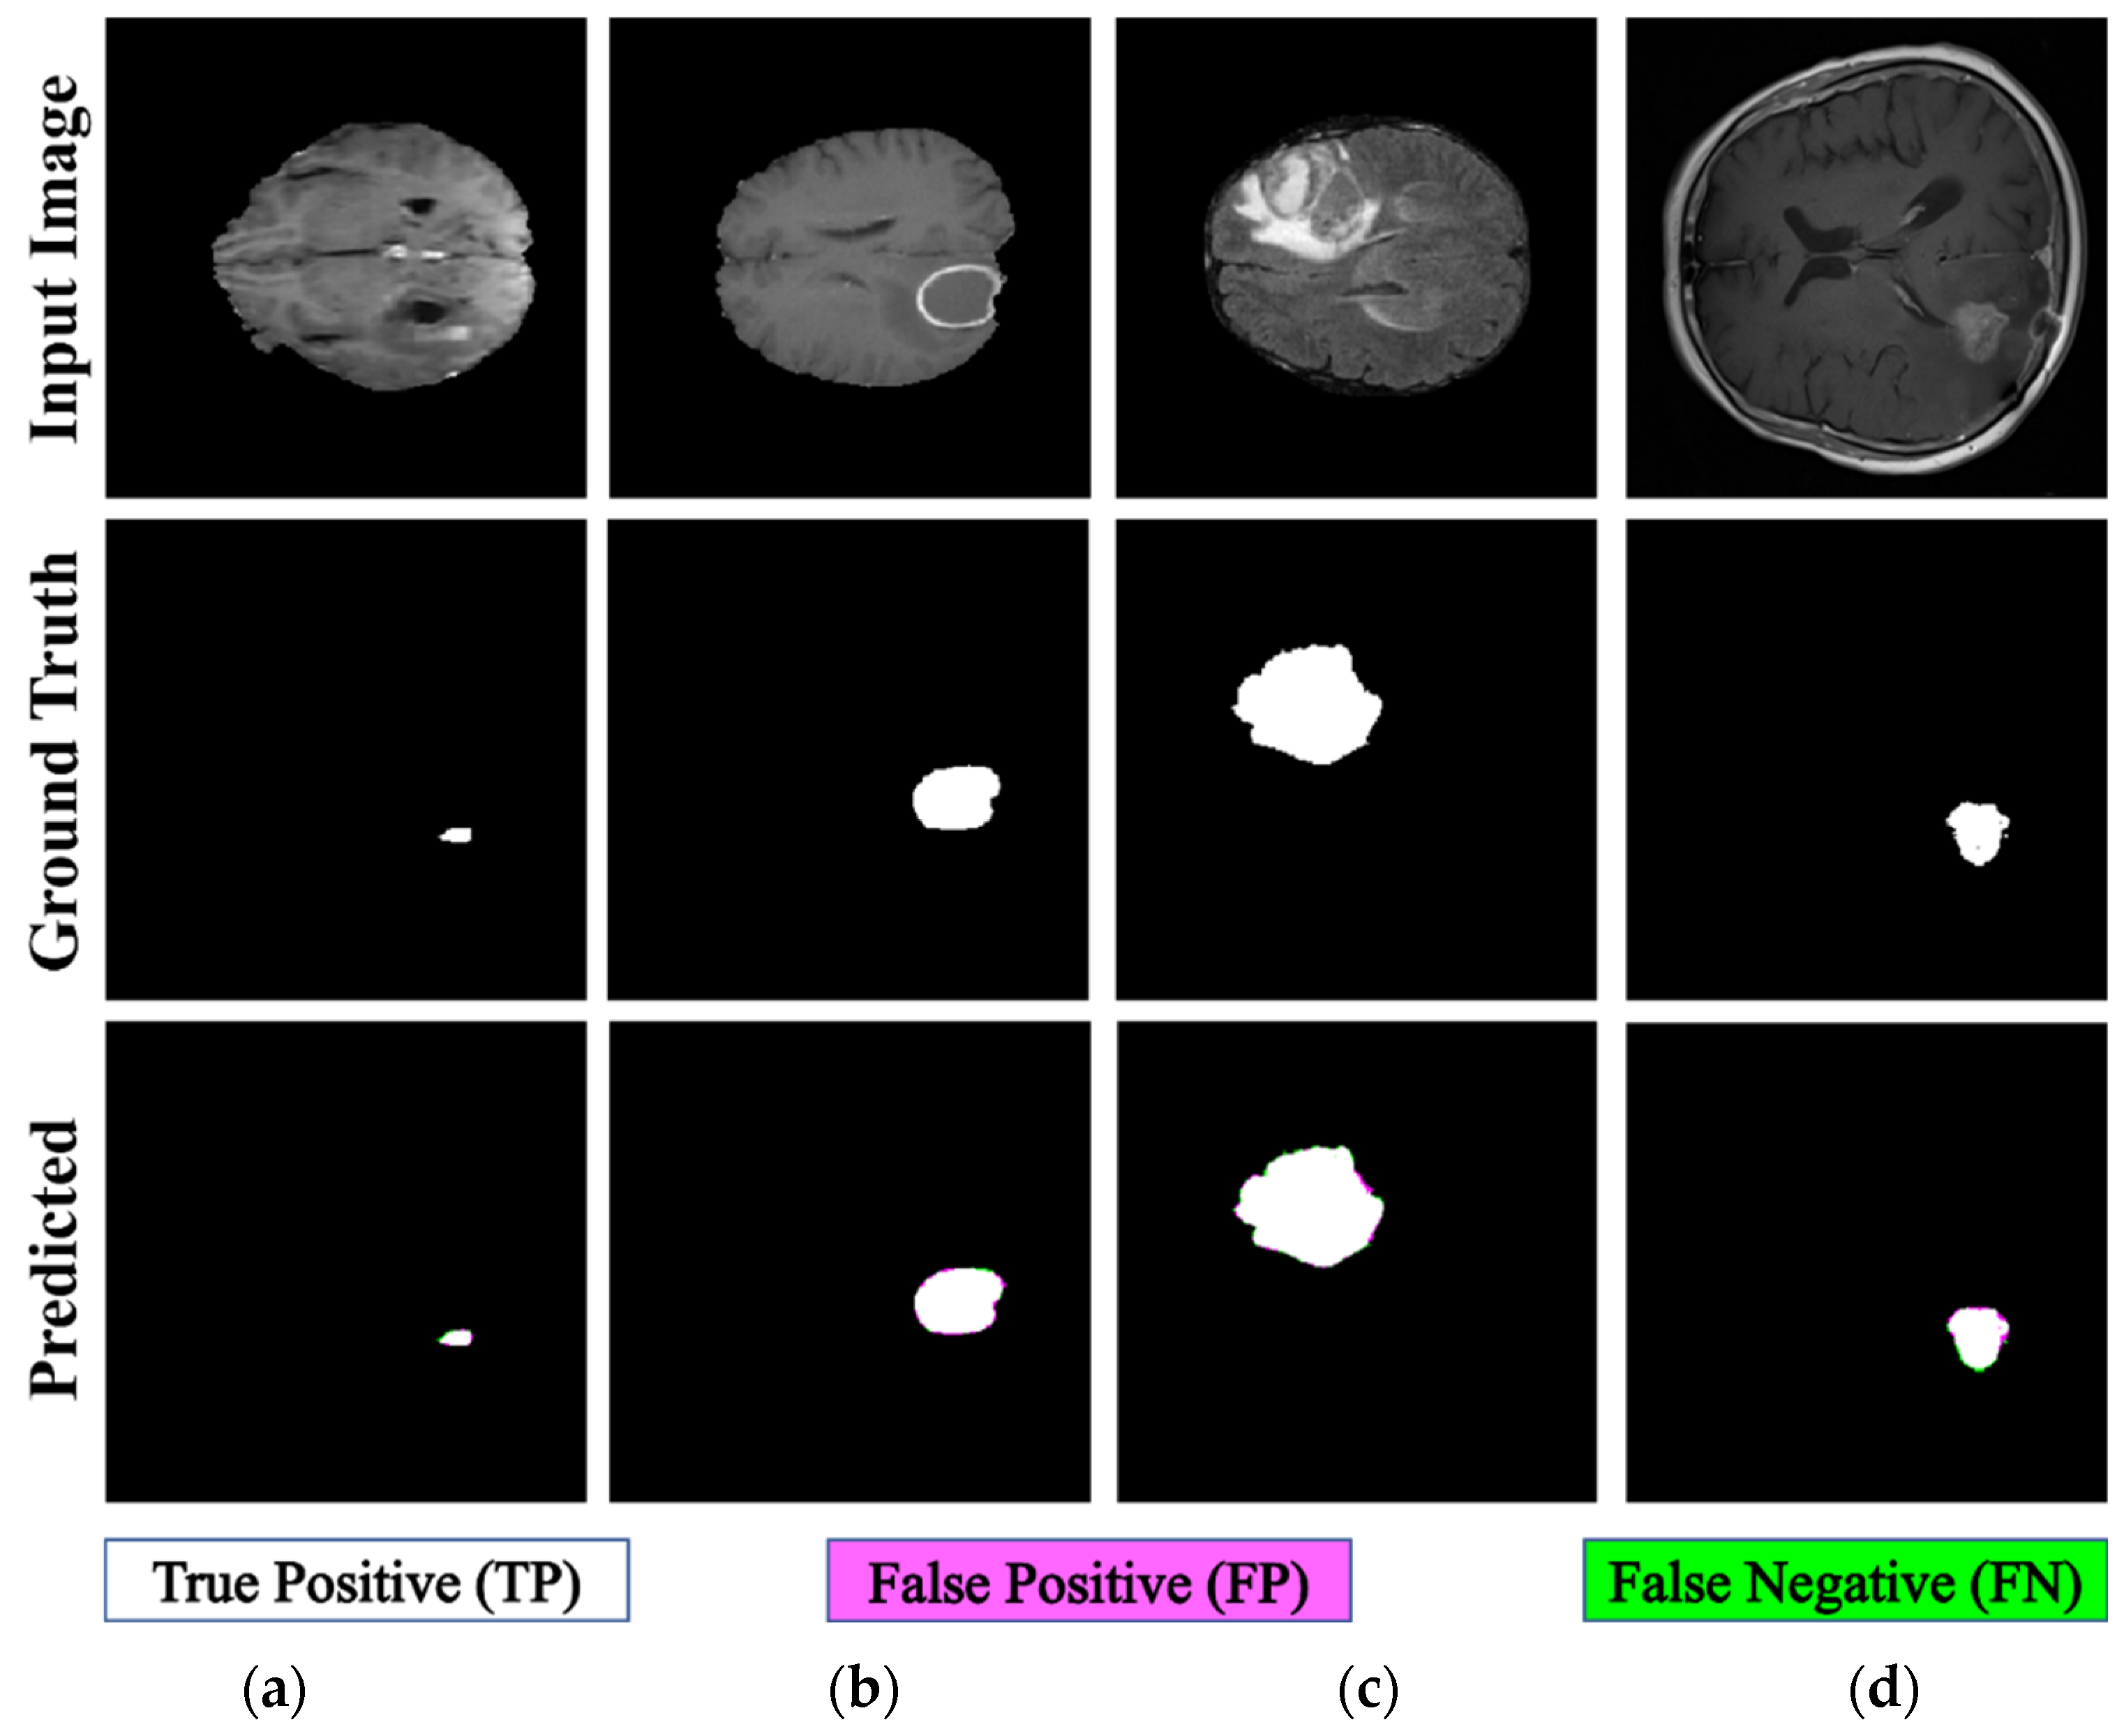

| Results | ET | TC | WT | Heterogeneous | ||||

|---|---|---|---|---|---|---|---|---|

| Figure 11a | Figure 11b | Figure 12a | Figure 12b | Figure 13a | Figure 13b | Figure 14a | Figure 14b | |

| FD | 1.1956 | 1.1312 | 1.2887 | 1.2562 | 1.5601 | 1.4406 | 1.0776 | 1.3711 |

| R2 | 0.957 | 0.934 | 0.983 | 0.96 | 0.982 | 0.98 | 0.983 | 0.954 |

| C | 0.9783 | 0.9665 | 0.9915 | 0.9799 | 0.9909 | 0.9901 | 0.9913 | 0.9768 |